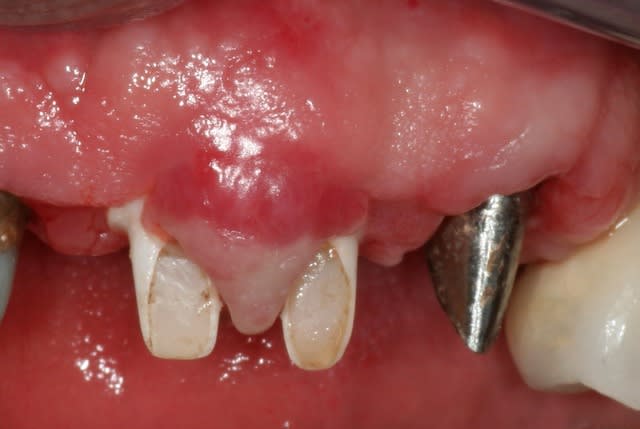

"et 2 beefsteak pour la dame", c'est un peu ce qui c'est passé cet aprem pour cette patiente qui m'a été adressé pour gérer une periimplantite à la mandibule. Et bien sûr, ceux qui ont planté, ne sont en rien préoccupé de l'absence de gencive attachée !! Pourquoi s'embêter, hein ? : t'ouvres, tu plantes et puis tu tractes comme un âne pour pouvoir fermer et puis si tu sutures le versant interne de la lèvre avec le plancher de la bouche ... ca marche pareil ... non?

Et donc mézigue aujourd'hui, avant de pouvoir assainir, a dû recréer un environnement gingival satisfaisant.

Y a en marre de rattraper les conneries des autres ! C'est pour ca que je poste ce cas. Ne faites pas comme ces "chirurgiens", mais pensez plutôt long terme. Si vous n'avez pas un environnement gingival satisfaisant d'emblée, gérer cela avant de passer à l'installation implantaire, c'est beaucoup plus facile à gérer par la suite. S'il vous plait !!

Donc pour en revenir à mon cas de cet aprem, en raison d'une absence complète de gencive attachée autour de ces 5 implants mandibulaires, et de par l'absence de vestibule, j'ai réaliser une double greffe gingivale libre de 15mm x 8mm chacune.

c'est de la demie épaisseur. Je n'ai pas de photos du site receveur avant mise en place du greffon dans le cas d cet aprem mais d'un autre cas (le principe est le même) où j'ai en plus pratiqué une implantoplastie :